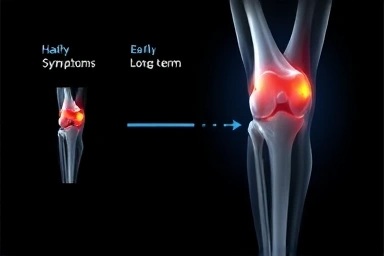

- 붓기, 통증, 뻣뻣함, 열감 등 증상 발생. 방치 시 연골 손상, 관절염 위험.

무릎 물 참은 관절 기능 이상 신호입니다. 활액막 자극으로 활액 과다 분비, 염증성 액체, 혈액 등이 축적됩니다. 방치 시 연골 손상 가속화, 퇴행성 관절염 위험이 2배 이상 증가합니다.

방치 시 최악의 시나리오

방치는 연골 영구 손상, 만성 관절염, 기능 상실로 이어집니다. 수술 가능성 증가, 2차 손상 위험도 높아집니다.

- 연골 손상 가속화, 만성 관절염 진행.

초기 치료 시 회복 속도 및 예후가 가장 좋습니다. 무릎 건강 '골든타임'을 놓치지 마세요.